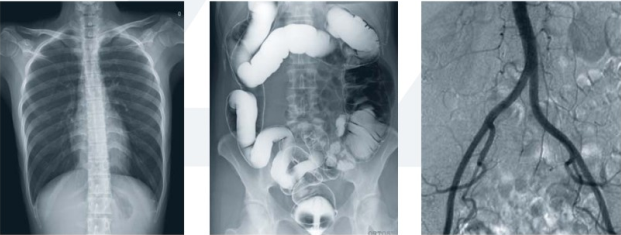

動(dòng)態(tài)DR是一種醫(yī)用X射線診斷醫(yī)療設(shè)備的名稱,相比于普通DR的單一功能,動(dòng)態(tài)DR集合拍片、造影、胃腸、透視等多種功能,大幅提高診斷效率,避免漏診、誤診。動(dòng)態(tài)DR近年來成為越來越多醫(yī)療機(jī)構(gòu)采購(gòu)設(shè)備的選擇,相比普通DR,動(dòng)態(tài)DR所創(chuàng)造的價(jià)值亦是有目共睹。隨著各大廠商陸續(xù)推出動(dòng)態(tài)DR產(chǎn)品,動(dòng)態(tài)DR已然成為一股趨勢(shì)。

動(dòng)態(tài)DR不局限于床式結(jié)構(gòu)或者胃腸檢查功能,而是更為廣泛的產(chǎn)品品類,結(jié)構(gòu)多樣,功能多樣。普通DR能做的診斷,動(dòng)態(tài)DR也能做,但動(dòng)態(tài)DR能做的診斷,普通DR不一定能做。那么,相比于普通DR,動(dòng)態(tài)DR具體有什么功能?

一、高清拍片功能

隨著醫(yī)學(xué)影像學(xué)科的綜合發(fā)展,當(dāng)今的X射線攝影常用于胸部病變的篩查,并可對(duì)炎癥、結(jié)核、腫瘤等進(jìn)行診斷;對(duì)腹部,還可以對(duì)膽道、泌尿系結(jié)石做出判斷;對(duì)四肢進(jìn)行拍片,看看骨骼肌肉系統(tǒng)的炎癥、結(jié)核、腫瘤,以及畸形、異物、外傷等。

二、大幅面透視功能

目前X射線透視主要用于胸部疾病的篩查以及常見體檢,可以觀察肺的呼吸運(yùn)動(dòng)、心臟和大血管的搏動(dòng)。這類檢查需要透視幅面大,17*17英寸大幅面是合適的,因?yàn)榇蠓鎸?duì)于觀察肺部呼吸運(yùn)動(dòng)、心臟和大血管的搏動(dòng)非常方便,只需要透視一次整個(gè)胸部一覽無余,醫(yī)生也能清晰的在透視圖像下進(jìn)行觀察和診斷。

三、高清點(diǎn)片功能

DR透視檢查還經(jīng)常用于對(duì)腹部病變的診斷,觀察膈下是否有游離氣體,以及判斷腸穿孔的可能性;依據(jù)腸腔積氣、積液的情況判斷胃腸道梗阻的位置及程度如何。還有,利用X射線透視查看異物的所在,以及節(jié)育環(huán)是否在位。這種情況下檢查不僅需要在透視下觀察還需要在必要的時(shí)候進(jìn)行點(diǎn)片,便于進(jìn)一步診斷,這就需要所用設(shè)備具有透視下點(diǎn)片功能。

四、視頻保存回放功能

在進(jìn)行胃腸道鋇餐檢查和鋇劑灌腸時(shí)須應(yīng)用透視,它除了觀察胃腸道形態(tài)外,還可觀察器官的活動(dòng),如:胃腸道的蠕動(dòng)與排空。在手術(shù)室有時(shí)也會(huì)用到它,如:術(shù)中定位,以及骨折、脫位病人的復(fù)位等。這種情況下的透視需要設(shè)備具有視頻保存的功能,防止造影劑的流速過快還沒來的及觀察就已經(jīng)錯(cuò)過,動(dòng)態(tài)DR可以通過視頻保存功能保存視頻,經(jīng)過視頻回放去觀察胃腸道的形態(tài)及器官的蠕動(dòng),可避免病人多次重復(fù)透視吃射線,又方便醫(yī)生的診斷。

五、可視化造影功能

X射線造影檢查有注射對(duì)比劑的泌尿系造影,包括:順行性靜脈腎盂造影、逆行性靜脈腎盂造影、膀胱造影、尿道造影;生殖道的造影,如:子宮輸卵管造影等,可對(duì)結(jié)核、腫瘤、畸形、外傷做出判斷;還可以利用造影對(duì)膽系、泌尿系的結(jié)石進(jìn)行判斷。此外,還可以通過鋇劑,對(duì)消化道進(jìn)行造影,如:食道鋇餐、上消化道造影、灌腸造影,可以對(duì)異物(魚刺、雞鴨骨頭)、靜脈曲張、潰瘍、結(jié)核、腫瘤、畸形做出判斷。以及一些竇道、瘺管進(jìn)行造影,察看其與周圍組織之間的關(guān)系。

六、全身拼接功能

全身拼接功能是在全景影像拍攝的情況下,拍攝各個(gè)部位的影像,合成一幅全景圖像。此功能操作簡(jiǎn)單、可自動(dòng)或手動(dòng)拼接,畸變率低,圖像均一無拼接痕跡等特點(diǎn),尤其適用于全脊柱和全下肢攝影,輔助脊柱畸形矯形治療、康復(fù)檢查,為臨床提供高準(zhǔn)確度圖像。全身拼接功能是現(xiàn)在醫(yī)院尤其是醫(yī)院特別看重的功能之一。